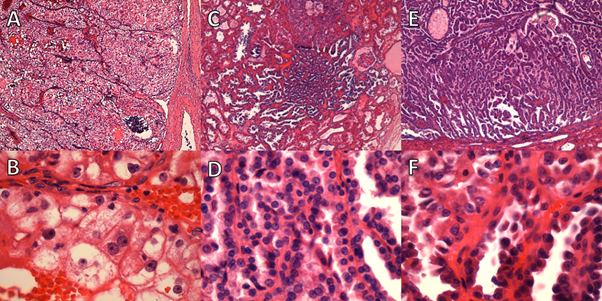

A nodular lesion present in the lower pole (50 mm at largest dimension) was classified as ccRCC (grade 4), with focal rhabdoid differentiation (Figure 4). This tumour showed some infiltration of renal sinus fat (Figure 2B). A second lesion in the lower pole (37 mm at largest dimension) was classified as a cc tubulopapillary RCC (low grade; Figure 5A-C). A third lesion in the lower pole (7 mm at largest dimension) was classified as multilocular cystic renal neoplasm of low malignant potential (Figure 5D-F). A 7-mm lesion in the upper pole was classified as mucinous tubular and spindle cell carcinoma (Figure 6). These tumours were limited to the kidney.

Figure 4

Figure 4. Case 2: A and B. Low-power fields showing clear cell renal cell carcinoma. C. High-power field showing rhabdoid differentiation. D. High-power field showing features consistent with a grade of 4.

Figure 5

Figure 5. Case 2: A-C. Clear-cell tubulopapillary renal cell carcinoma. D-F. Multilocular cystic renal neoplasm of low malignant potential.

Figure 6

Figure 6. Case 2: A. Low-power and (B) high-power fields showing mucinous tubular and spindle cell carcinoma.